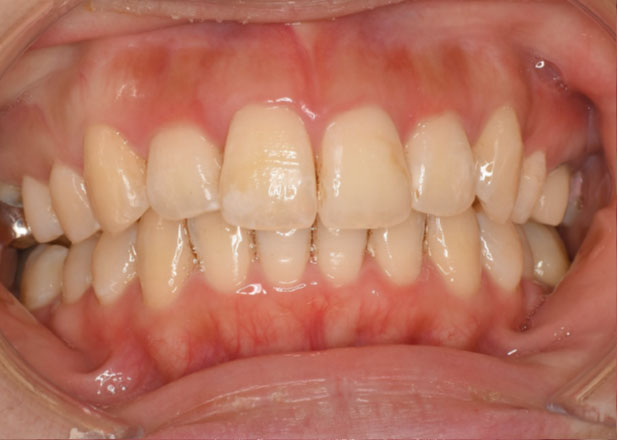

治療後

マウスピース矯正 マウスピース矯正 マウスピース矯正

かみ合わせの不調により痛みも生じている状態でしたが治療後は痛みをなく経過良好です。

今回は前から4番目の歯を1本抜歯して治療を行いました。

必ずしも歯を抜かないと矯正治療ができないというわけではありませんが「笑顔やお顔とのバランス」を考慮し、今回は抜歯を提案させていただきました。